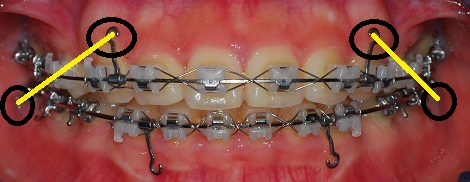

정면사진입니다.

와 진짜 가지런해여ㅋㅋㅋㅋㅋ

고무줄은 하악에 맨 뒤 치아 브라켓과 상악에 고리에 거는 것입니다.

위 아래 고무줄을 걸면 입을 벌리기가 어렵기 때문에 식사할 때만 빼고 다시 열심히 고무줄을 걸어야 합니다.